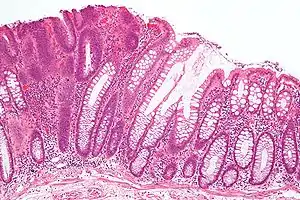

| Micrograph of a tubular adenoma (left of image), a type of colonic polyp and a precursor of colorectal cancer. Normal colorectal mucosa is seen on the right of the image. H&E stain. | |

Adenoma is a benign tumor of glandular tissue, such as the mucosa of stomach, small intestine, and colon, in which tumor cells form glands or gland like structures. In hollow organs (digestive tract), the adenoma grows into the lumen - adenomatous polyp or polypoid adenoma. Depending on the type of the insertion base, adenoma may be pedunculated (lobular head with a long slender stalk) or sessile (broad base).

The adenomatous proliferation is characterized by different degrees of cell dysplasia (atypia or loss of normal differentiation of epithelium) irregular cells with hyperchromatic nuclei, stratified or pseudostratified nuclei, nucleolus, decreased mucosecretion, and mitosis. The architecture may be tubular, villous, or tubulo-villous. Basement membrane and muscularis mucosae are intact.